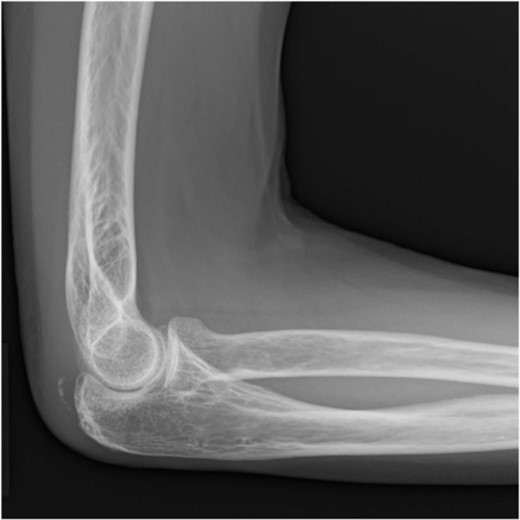

A 65-year-old healthy Japanese woman fell on her hands with her right elbow extended. She presented to our hospital with pain and swelling in the right elbow joint; active extension was impossible. X-rays showed a triceps tendon avulsion fracture (Fig. 1). Her bone mineral density, using dual X-ray absorptiometry, was 71% of the young adult mean for the lumbar spine. She was diagnosed with an avulsion fracture of the right olecranon (AO classification: 2U1A1) and underwent surgery 7 days post-injury.

Plain radiographs of the right elbow show no abnormal findings in the anteroposterior view (A); however, an avulsion fracture of the olecranon is observed in the lateral view (B).